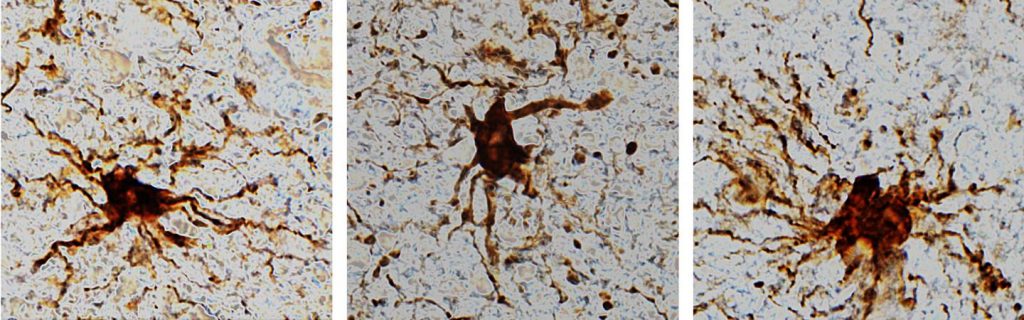

Iets opmerkelijks zagen de onderzoekers in een derde groep genen, betrokken bij de activiteit van gliacellen (de steun- en afweercellen van het brein): de cellen vertoonden juist een enorme piek aan gen-activiteit. De gliacellen namen daarnaast flink in omvang toe en groeiden zelfs nieuwe uitlopers (armachtige structuren).

Toch is dit geen gek, onverwachts resultaat. Gliacellen spelen een grote rol bij de afweer van de hersenen en worden geactiveerd door schade en ontstekingen, als het brein kampt met een zuurstoftekort. De gliacellen worden opgetrommeld en proberen de boel zo lang mogelijk te redden.

“Op het moment dat iemand overlijdt zullen cellen reageren op het feit dat er geen bloeddoorstroming meer is, en er dus geen voedsel meer aangevoerd wordt,” vertelt Hol. “Het verbaast me ook niet dat de genetische activiteit van gliacellen omhooggaat. Op het moment dat er neuronen afsterven zullen eerst de microglia en later astrocyten (twee types gliacellen, red.) reageren.”